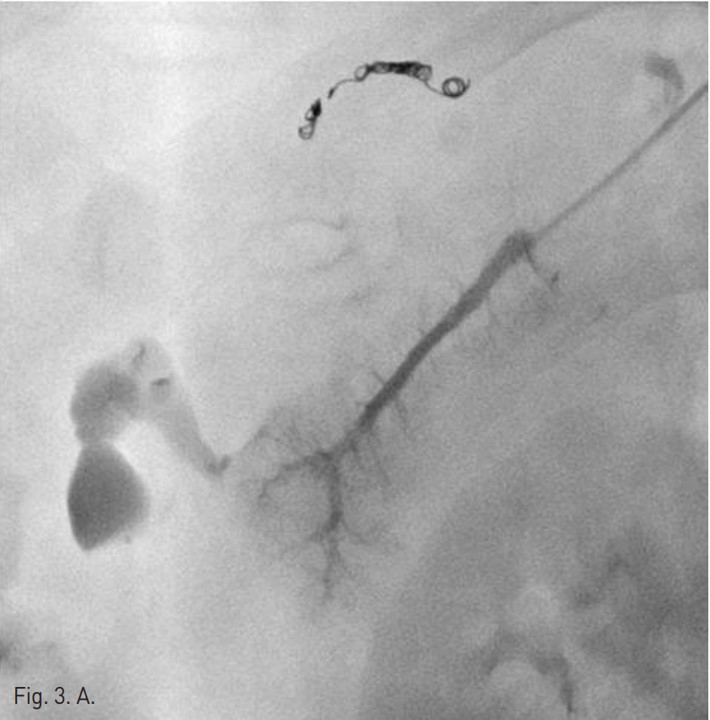

간동맥 혈관 조영을 하기 위해 오른쪽 대퇴동맥 주변을 국소 마취 후, angiocath로 대퇴동맥을 puncture하고 guidewire유도 하에 RH catheter삽입 후 celiac trunk를 선택하여 간동맥 혈관조영을 시행하였다. 간동맥 혈관 조영상에서 분명한 출혈은 보이지 않았지만, right anterior superior hepatic artery에서 arteriovenous shunt가 있어 microcatheter(Sirabe 2.2 Fr)로 간동맥을 선택하여 microcoil (TORNADO microcoil, 4 mm x 2mm, 3 mm x2 mm and 5 mm x 2 mm)과 gelfoam을 이용하여 색전술을 시행하였으나(Fig. 2) 색전술 4시간 후 수축기 혈압이 60 mmHg로 감소되었다. 간동맥 색전술에도 불구하고 계속적인 출혈이 있어서 간문맥 출혈을 의심하였음. Chiba needle로 좌측 간문맥을 puncture하고 guide wire유도 하에 angiography catheter를 삽입하여 간문맥 혈관 조영술을 시행하였다. 간문맥 혈관 조영에서 right anterior inferior portal branch에서 출혈이 관찰되어 microcatheter(Sirabe 2.2 Fr)로 right anterior inferior portal branch를 선택하여 두 개의 microcoil (Nester 35 mm x 4 mm and Tornado 5 mm x 2mm), Glue(Histoacryl 0.5ml) 그리고 Gelfoam을 이용하여 색전술을 시행하였다 (Fig. 3).

Fig. 3. A

Fig. 3. A. Direct portogram shows active bleeding (arrow) from the right anterior inferior portal branch.